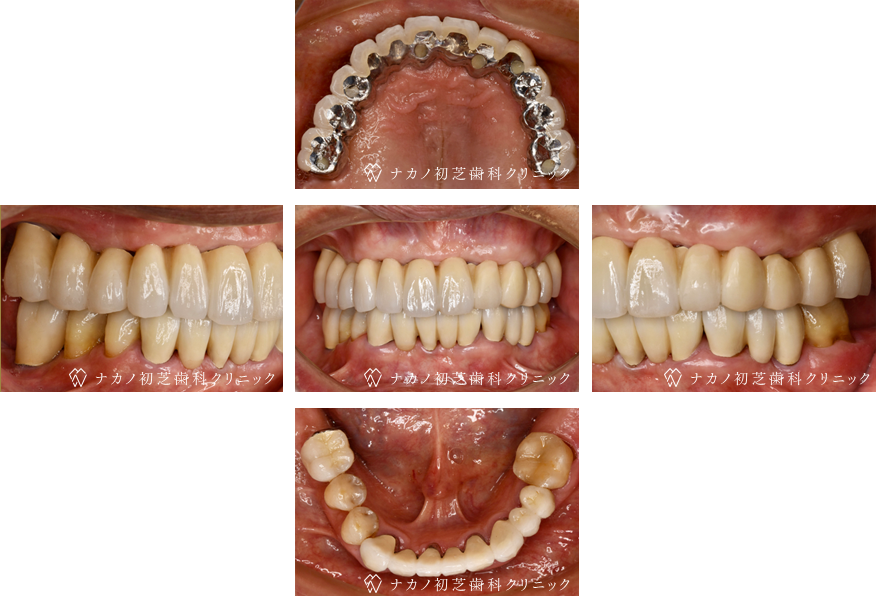

インプラント・13本 (60代女性)

AFTER

年齢 60代女性

治療内容 インプラント治療13本(骨造成の併用)

インプラント治療とは、歯を抜いた所にチタン製の人工歯根を埋入し、その上に歯を入れる方法です。骨を増やすことで、より審美的に治療が出来ました。費用 1本 400,000円(税込 440,000円)

リスク・副作用

腫れ・疼痛・違和感を感じるなどの症状を生じることがあります。